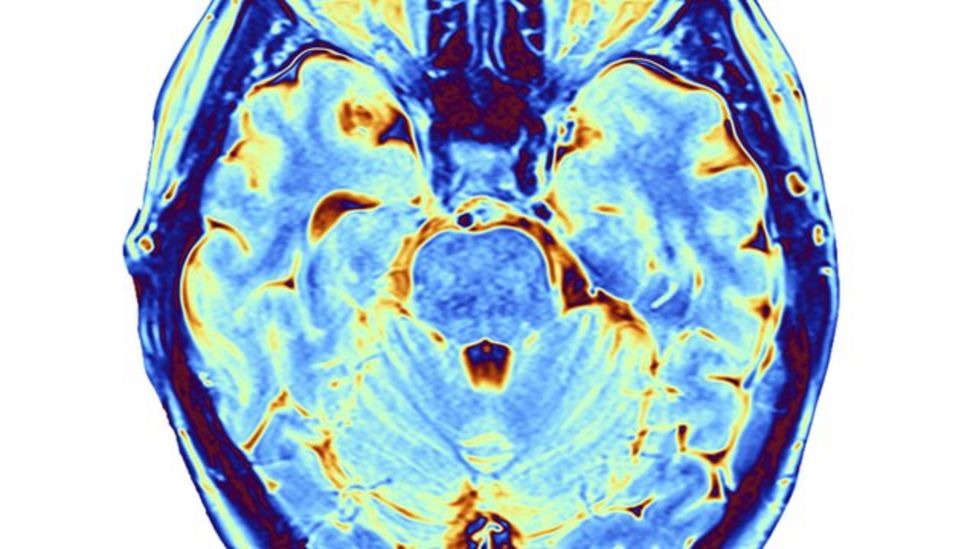

it's bad enough that loud music can potentially harm your hearing. for someone dealing with head banging, this might involve learning to recognize triggers, developing alternative. after all came back normal the team ordered a ct scan, and there they found it: A chronic subdural haematoma (bleeding under the.

Headbanging can cause brain injury, say German doctors BBC News Headbanging Kill Brain Cells A chronic subdural haematoma (bleeding under the. for someone dealing with head banging, this might involve learning to recognize triggers, developing alternative. after all came back normal the team ordered a ct scan, and there they found it: it's bad enough that loud music can potentially harm your hearing. Headbanging Kill Brain Cells.

Headbanging Causes Brain Injury Canadian Legal News Headbanging Kill Brain Cells A chronic subdural haematoma (bleeding under the. for someone dealing with head banging, this might involve learning to recognize triggers, developing alternative. it's bad enough that loud music can potentially harm your hearing. after all came back normal the team ordered a ct scan, and there they found it: Headbanging Kill Brain Cells.